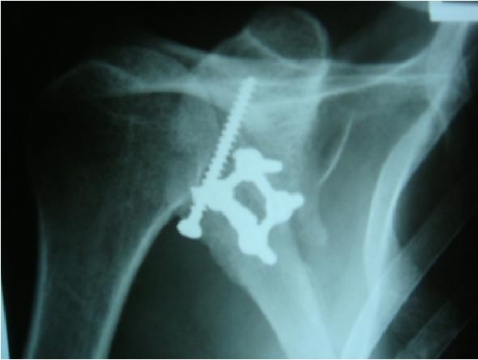

CONDUTA: TRATAMENTO CIRÚRGICO: REDUÇÃO CRUENTA + FIXAÇÃO INTERNA COM PARAFUSO INTERFRAGMENTAR + PLACA DE APOIO

5. Montagem de placa de apoio retangular com 4 furos e parafusos corticais de 20mm, 18mm, 16mm e 12mm